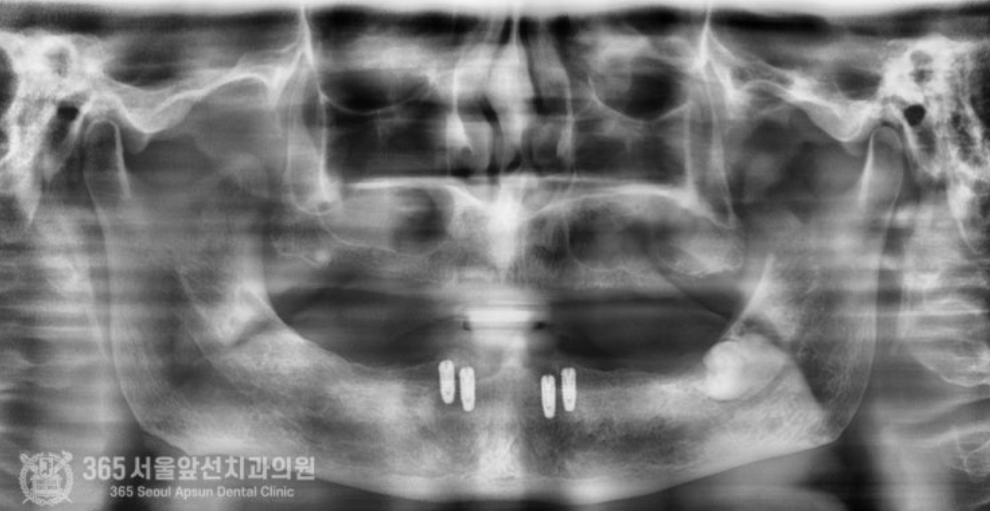

촬영일시 : 2024.06.14 기다리는 과정에서 문제가 없는지 체크도 꼼꼼히 합니다. 문제 없이 잘 진행되어 가고 있네요 좋습니다ㅎㅎ 이제 시간이 지나서 임플란트가 뼈와 단단하게 붙었다고 판단되기에 본을 뜨기 위한 단추를 달아줍니다. 전문적인 용어로는 2차 수술이라고 하는 과정입니다. (윗 부분 사진) 아랫부분 사진을 보시면 임플란트가 뼈와 단단하게 붙었구요. 이제 본을 뜨기 위해 단추를 달아줍니다ㅎㅎ 이제 거의 다와갑니다. 단추를 달아주고 본을 떠서 아래 틀니를 붙잡아줄 튼튼한 임플란트 브릿지를 먼저 만듭니다.